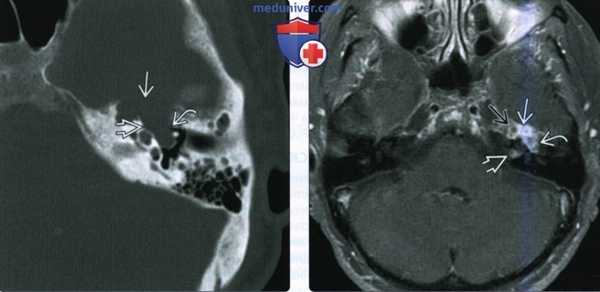

(Слева) При аксиальной КТ в костном окне у пациента с правосторонним параличом лицевого нерва визуализируется маленькая ВМЛН в ямке коленчатого ганглия. Обратите внимание на точечные костные очаги в структуре, которые позволяют отличить ВМЛН от шванномы лицевого нерва, которая также возникает преимущественно в ямке коленчатого ганглия.

(Справа) При аксиальной МРТ Т1 С+ FS у этого же пациента определяется ВМЛН, накапливающая контраст, в области коленчатого ганглия. Область точечных кальцинатов выглядит как гипоинтенсивный фокус.